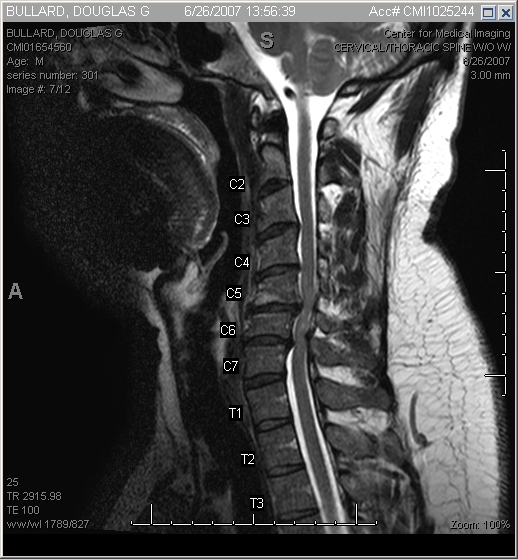

The end result - artifical discs. The old discs have been removed, the offending bits of bone removed, and the new joints inserted.